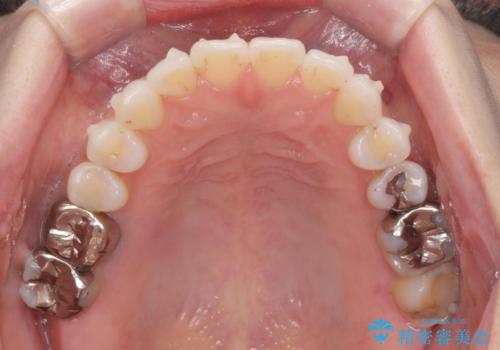

- 突き出た前歯の角度を改善したい、と矯正治療を希望され来院されました。

抜歯を行いワイヤー矯正で2-3年程度の時間をかけて、しっかり前歯を後方に移動させるか、

抜歯を行わずにIPR(歯の間に空隙を設ける)で可及的に角度の改善を行うか、

2通りの治療方針をご提案しました。

治療期間が約半年で行うことができ、歯を抜かずにマウスピース矯正で可及的に前歯の角度を改善する治療方針を

奥歯の状態等も鑑みて選択されました。

約半年で大きく前歯の角度を改善することができ、抜歯を行わない矯正治療の結果に大変喜んでいただくことができました。